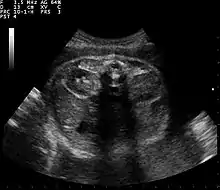

بالفحص الروتيني أثناء الحمل عن طريق التصوير بالموجات فوق الصوتية يتم اكتشاف غياب الكلى، وكذلك يمكن تشخيصه بالأشعة المقطعية والتصوير بالرنين المغناطيسي[4]